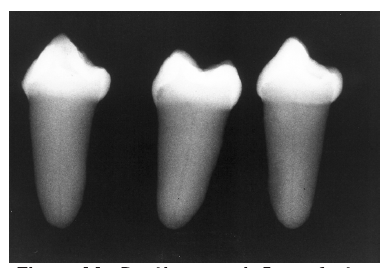

Dentin caries extends into the tooth dentin and can be recognized by noting the focal loss of dentinal radiopacity. Most commonly, this darkened dentin is located beneath carious enamel and, typically, the lateral dimension of the dentinal involvement exceeds that of the associated enamel caries (Figure 3). Dentin caries may be discerned interproximally, on the occlusal surface, buccally/lingually, or on root surfaces.

Figure 3 - Dentin Caries

Figure 3